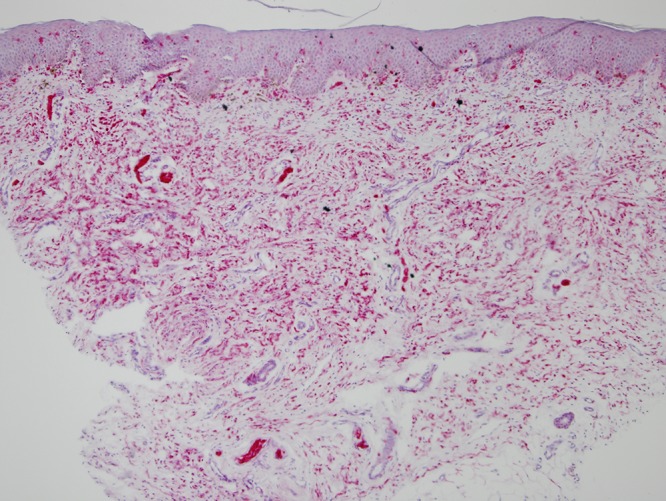

Punch biopsy of the soft plaque on the lower back revealed a proliferation of spindle cells in the dermis, arranged in fascicles. The majority of fascicles were wavy and surrounded by stroma consisting of thin, delicate connective tissue fibers (Figure 2A). Cells throughout the dermis stained positive for S-100 (Figure 2B) and negative for MelanA (not shown), compatible with the diagnosis of a neurofibroma.

Figure 2.

(A) H&E stained tissue section from SNF lesion on the lower back at 10× magnification, showing proliferation of spindle cells in the dermis, arranged in fascicles. The majority of fascicles are wavy and surrounded by stroma consisting of thin, delicate connective tissue fibers. (B) S100 stained tissue section from SNF lesion on the lower back at 10× magnification, with cells throughout the dermis staining positive for S100. [Copyright: ©2015 Helfand et al.]